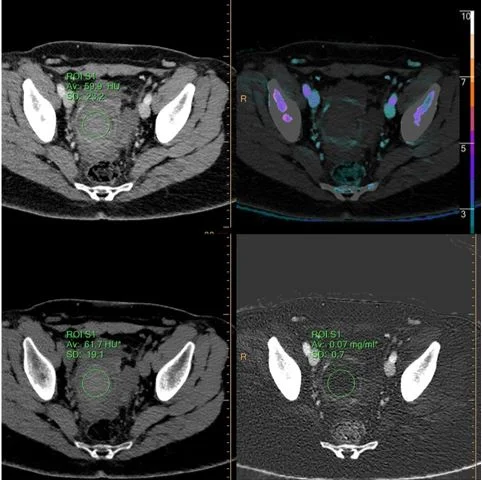

Urinary stone composition